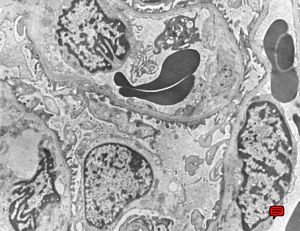

M,13y. | thin basement membrane syndrome